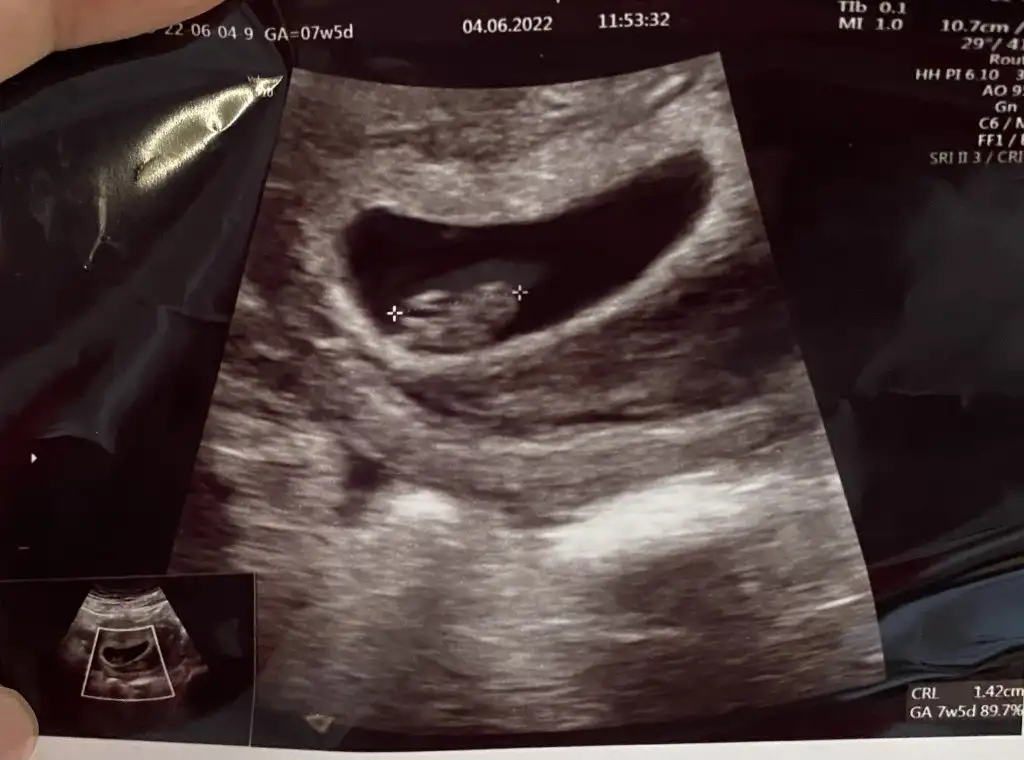

Benim içinde yorum yaparsanız sevinirim vajinal ultrason 6+3Selam Kızlarbir çok kişi gruplardan beni bilir. Yine yetiştim imdatlara

5 ve 14. haftaya kadar olan ultrason fotolarınızı paylaşın. Vajinadan mı yoksa karından mı çekildiğini ve kaç haftalık olduğunu da mutlaka belirtin.

yolk sac çok büyük, yorum yapamamBenim içinde yorum yaparsanız sevinirim vajinal ultrason 6+3

Cuma günü kontrolüm var o zaman tekrar bakarsanız sevinirim.yolk saç çok büyük derken kötü bir durum muyolk sac çok büyük, yorum yapamam

yeni hamile annelerimiz ilk önce yolk sac oluşur sonra bebek oluşur, normal bir durumCuma günü kontrolüm var o zaman tekrar bakarsanız sevinirim.yolk saç çok büyük derken kötü bir durum mu